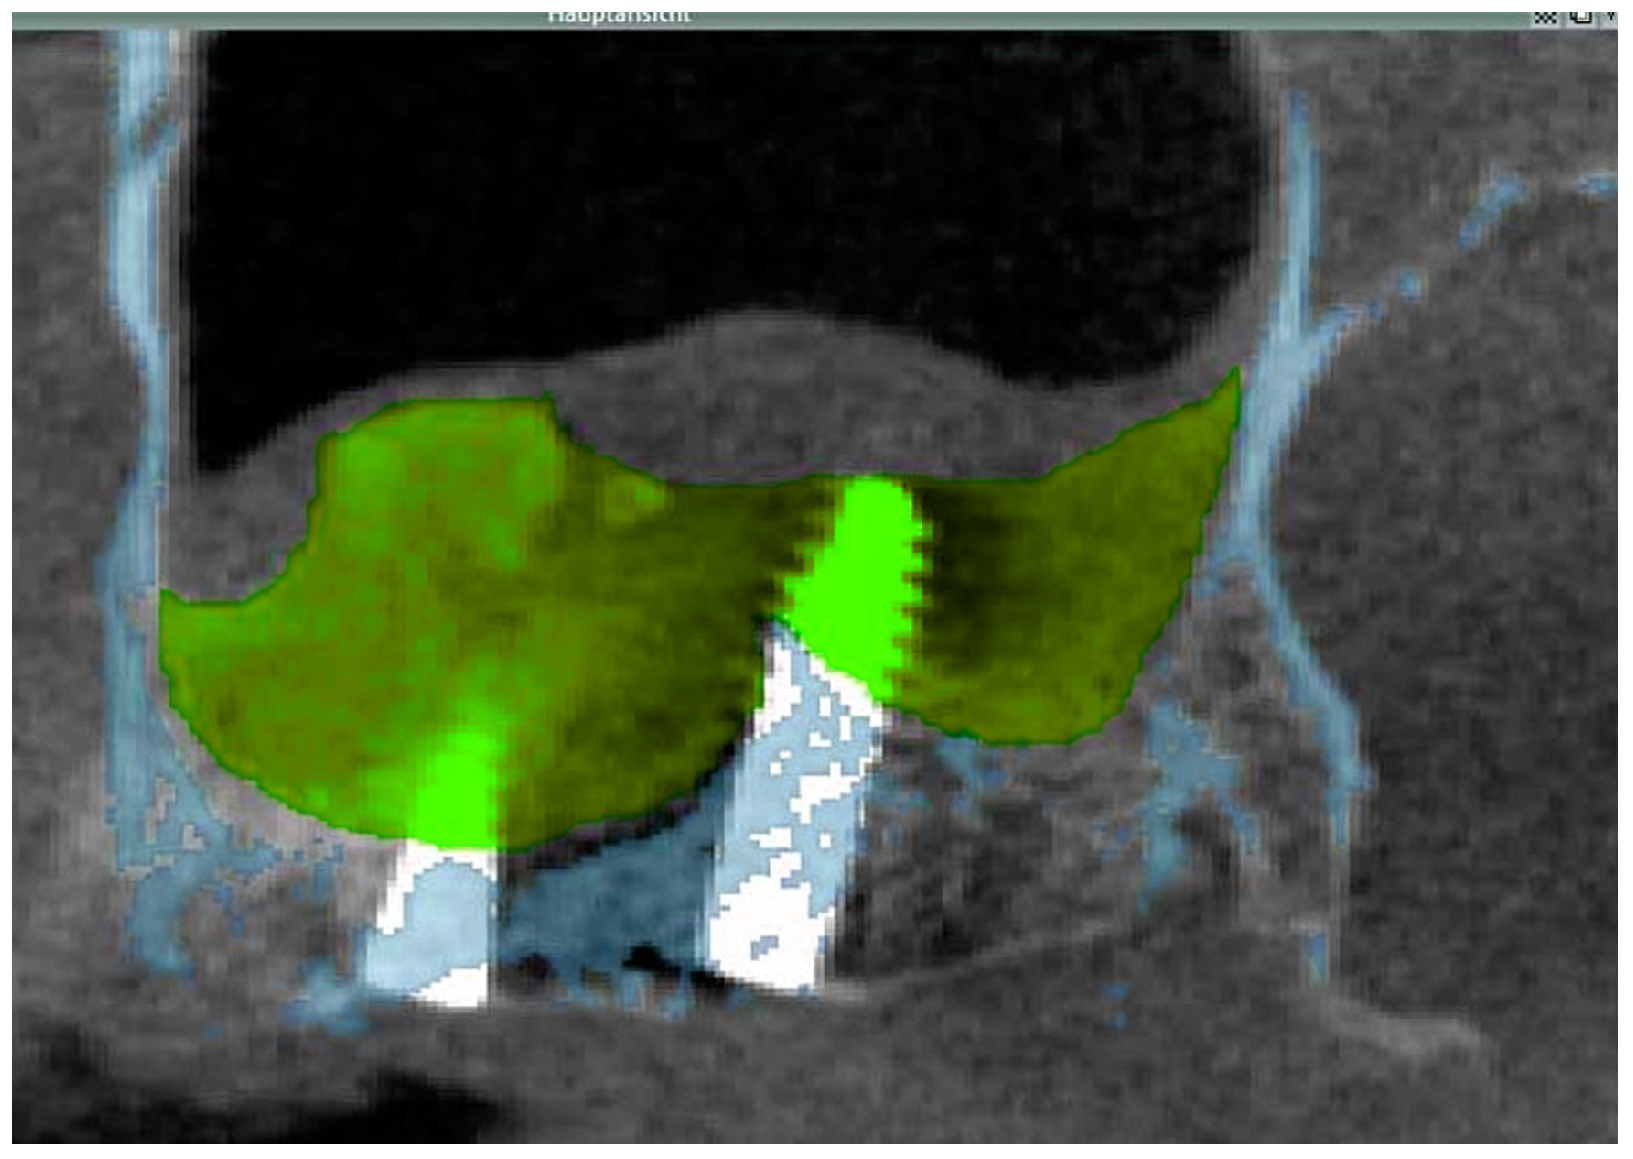

2.3.1. Cone Beam CT

2.3.2. Data Transfer, Analysis and Volume Determination

3.2. Radiological Results